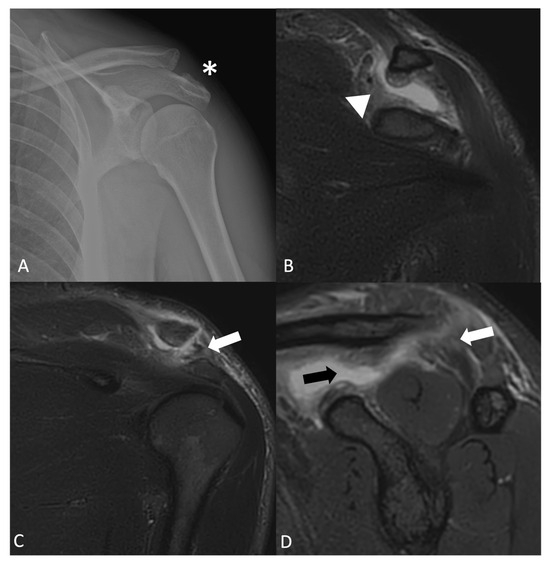

Acromioclavicular (AC) joint dislocation (Figure 6) may present as a bump above the AC joint [30].

Figure 6.

(A) AP X-ray, (B,C) coronal STIR, and (D) sagittal STIR in a patient with type III acromioclavicular dislocation according to the Rockwood classification. There is a rupture of both the acromioclavicular (white arrows) and coracoclavicular ligaments, trapezoid ligament rupture (black arrow), and conoid ligament rupture (arrowhead), causing complete dislocation of the joint (asterisk).

The severity of AC joint dislocation is classified using the Rockwood classification system, with types I to VI representing increasing degrees of ligamentous disruption and joint instability [31]. Bony bumps are often seen in non-traumatic bones. Osgood-Schlatter (OS) disease (Figure 7) is a traction apophysitis due to the repetitive contraction of the quadriceps femoris muscle, which affects the patellar tendon, which in turn exerts traction against the tibial tubercle [32]. This condition is most common in children and adolescents who play sports, and it is more frequent in males than in females [33].